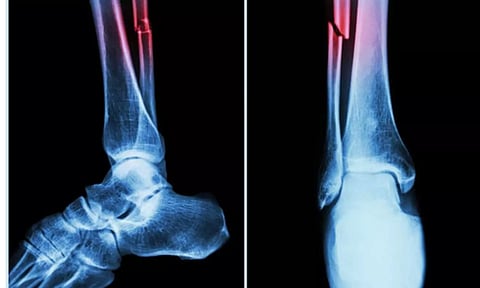

The study, published in the Journal of Orthopaedic Research, suggested that people with Covid‐19 may experience long‐term orthopaedic issues, such as decreased bone mass, increased fracture risk and other musculoskeletal complications.

In the study, mice who had Covid-19 showed significant bone loss. This loss decreased the bone mechanical strength and increased the risk of fractures.

The study suggested that the higher risk of fragility fractures, when a person falls from standing height or less, may be one of the underreported long-haul symptoms of Covid.